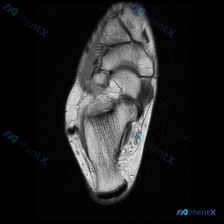

看到这个挺有代表性的病例,整理出来和大家分享一下思路。 病例基础信息 问题是:患者有膝前痛症状,临床怀疑软骨异常,提供了一张膝盖MRI-T1加权轴位图像,问图像里能看到什么病变。 影像读片结果 我们先看这张图像本身: 1. 扫描层面:膝关节上方,显示髌骨和股骨远端髌股关节面 2. 骨质结构:股骨远端...

刚看到这个病例,是临床怀疑膝关节软骨异常,只提供了一张膝关节髌股关节层面的轴位T1加权MRI,整理一下分析思路分享给大家。 一、病例与影像基本信息 本次仅提供单张膝关节MRI轴位T1序列影像,临床核心疑问是评估是否存在软骨异常,未提供患者病史、症状及其他临床资料,也未提供其他序列/切面的MRI影像。...

今天看到这个挺有讨论价值的读片问题,整理了完整信息和分析思路分享给大家。 病例/影像基本信息 这是一张膝关节轴位T1加权MRI图像,临床提出的问题是评估是否存在软骨异常。 我们先看这份影像的客观观察结果: 1. 整体解剖结构:髌骨、股骨远端滑车轮廓清晰,皮质骨光滑,无骨质破坏或骨皮质中断,骨髓信号大...

刚看到这个有意思的影像病例,整理一下完整资料和分析思路给大家参考。 病例基本信息 这是一张膝关节MRI T1加权轴位扫描影像,核心问题是:临床提示存在「软骨异常」,需要解读影像表现并分析原因。 影像客观评估结果 先给大家说客观的影像发现: 1. 骨性结构:股骨远端滑车、髌骨的骨皮质完整,松质骨髓信号...